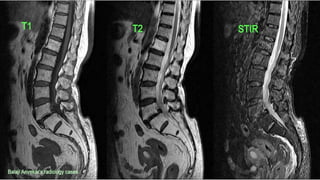

Spine sequences

• T1

• T2

• STIR

• T1C

• DIXON

• DWI

• SWI

59